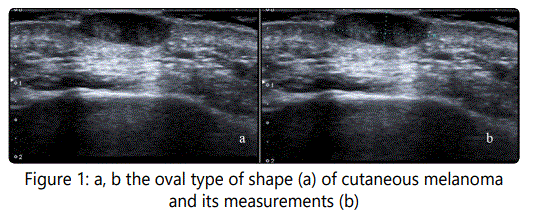

Analyzing all 27 cutaneous ultrasound images we clearly found two main types of melanoma mass shapes: nodular (Fig 1a) and superficial (Fig 2a). Definition and thickness measurements in both groups are quite easy (Fig 1b, 2b). In some superficial or linear shape types of malignant melanoma, we found also intermediate cases with the part of the tumor starting its asymmetric vertical jagged growing (Fig 3a). This jagged type can be in any place of the superficial melanoma: in the middle, in the end, or in one or two parts of the linear shape of the mass. The measurements had to be appropriate and included its deepest part (Fig 3b). Taking into consideration not only the radiological aspects but the clinical point as well, it is more convenient to analyze the cutaneous melanoma group according to 3 shape types of tumor: oval shape, jagged shape, and linear shape. We also registered the ratio between the diameter of the mass and its maximal thickness - L/T ratio.

We divided the ultrasound criteria for 27 malignant melanoma cases into 3 groups (Table 1).

14 patients (51,9%) with an oval shape, 7 patients (25,9%) with jagged shape and 6 patients (22,2%) with linear or superficial tumor shape.